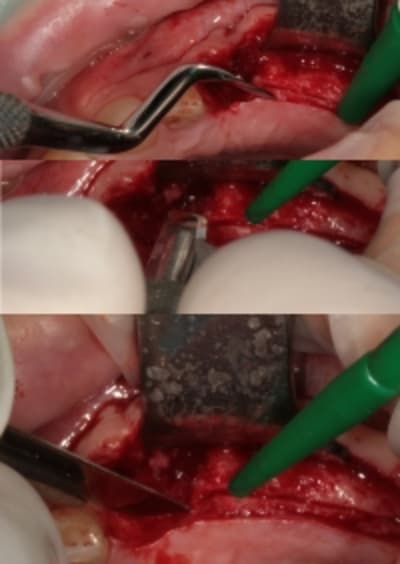

;Les photos:

1:

état initial,

disque diamanté

scie circulaire

2:

Ostéotome "lame" angulé

lame 15 (fréquent dans ce cas )

Ostéotome droit

tous sont manipulés avec douceur, mais aussi impactés avec le maillet chirurgical